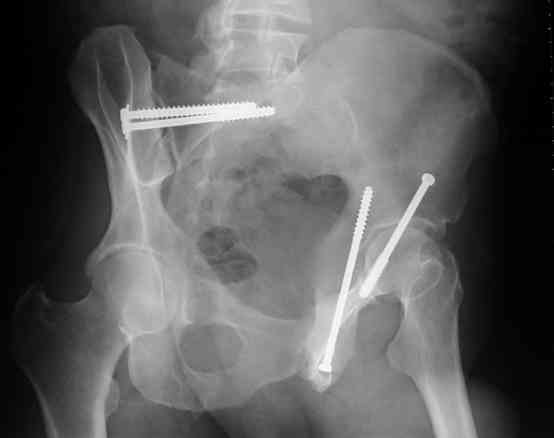

45 yo male in MVA, only other injury=small subarrachnoid bleed (neurologically fine, GCS never <14), with this transverse & associated posterior wall fx-dislocation 7/7

In skeletal traction thru distal femoral pin 40 lbs with decent reduction - except for the free fragments in the hip joint. ORIF planned for post-injury day 11.

I'll include a few images of a similar injury in a similarly large male patient. This patient "showed up" in our ER c/o hip pain 2 months after being treated in the lateral position, without a quality reduction, without an anterior column transverse supporting implant, with an unbalanced plate applied too medially, with insufficient caudal segment fixation...it took over 8 hours and a 3+ l blood loss to debride the callus from front then

back, excise the HO, release his sciatic nerve, reduce the head-transverse-wall, and fix it...and now it's a staging procedure.